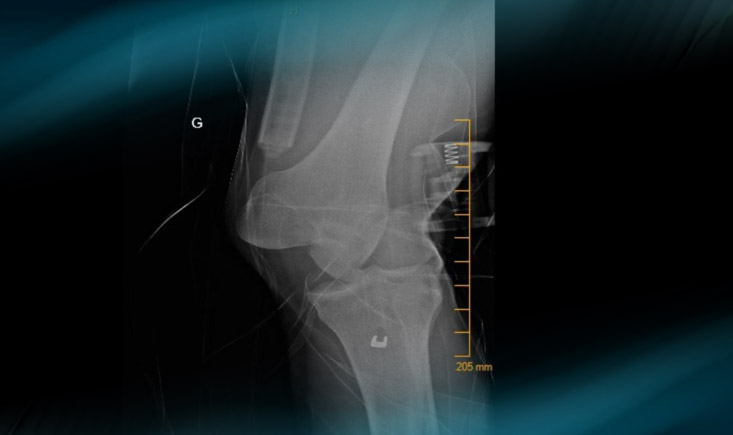

X-Ray at his arrival to the ER